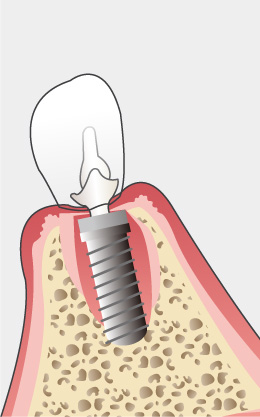

インプラント治療とは術前診査・診断を十分に行った上で、歯が抜けてしまった部分にインプラント(人工歯根)を埋め込み、その上から自然な見た目の人工歯を装着させるという治療法で、骨にしっかりとインプラント(人工歯)を定着させるため、自分の歯のようにしっかり、思い切り噛めるようになります。